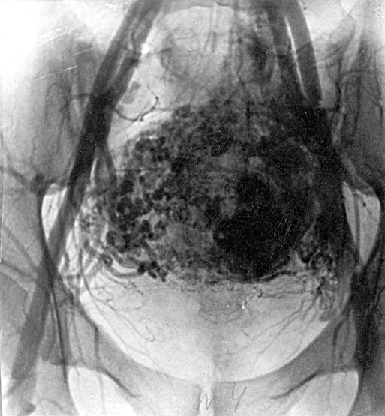

Общеизвестна способность трофобластических опухолей к метастазированию даже при отсутствии морфологических признаков злокачественности. Так, наблюдая за 97 больными пузырным заносом, Chan обнаружил у 10 из них метастазы в легких. Как известно, трофобластическая опухоль метастазирует гематогенным путем, преимущественно в легкие и влагалище, реже в другие отдаленные органы — печень, почки и головной мозг. По данным литературы, метастазы хориокарциномы обнаруживаются в легких в 57–80% случаев, во влагалище — 30%, головном мозге — 17% и печени — 10%. Тем не менее метастазы опухоли теоретически могут быть в любом органе, в т.ч. в средостении, кишечнике, коже и т.д.

Рисунок 2. Метастазы трофобластической опухоли в легкие